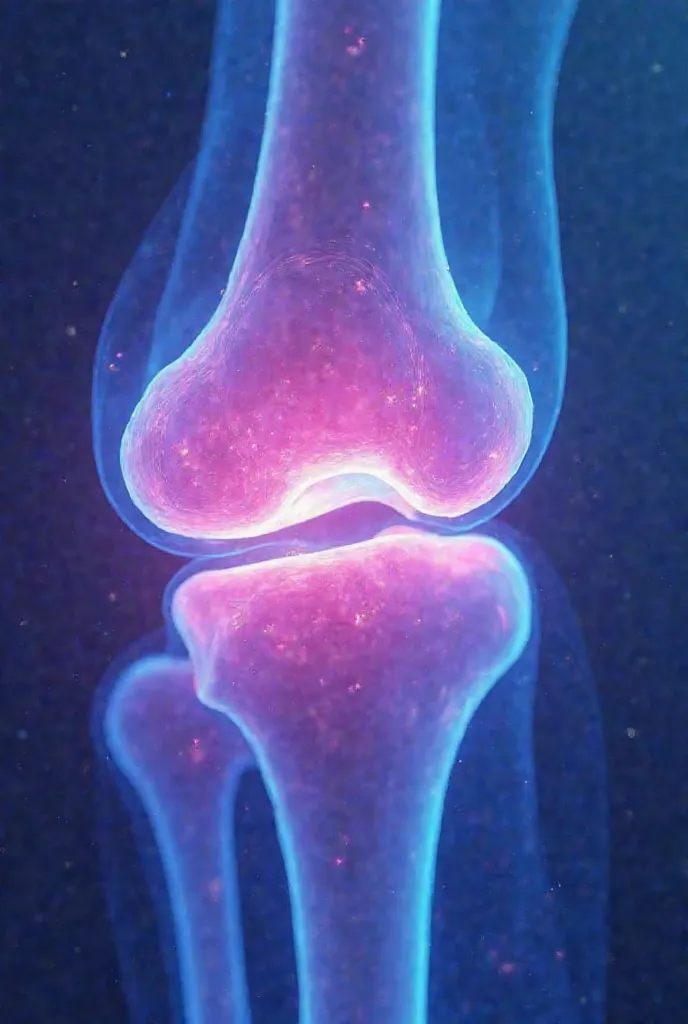

Close-up of human knee,There is a bone in the middle, knee, Knees, surreal bone structure, Protruding bones, Realphotos, orthographic view, Look across the shoulder, medical depiction, Osteoarticular joints, computer generated, hyper realisitc, sharp bone structure, joint, digital painted

Close-up of human knee

medical depiction

Osteoarticular joints